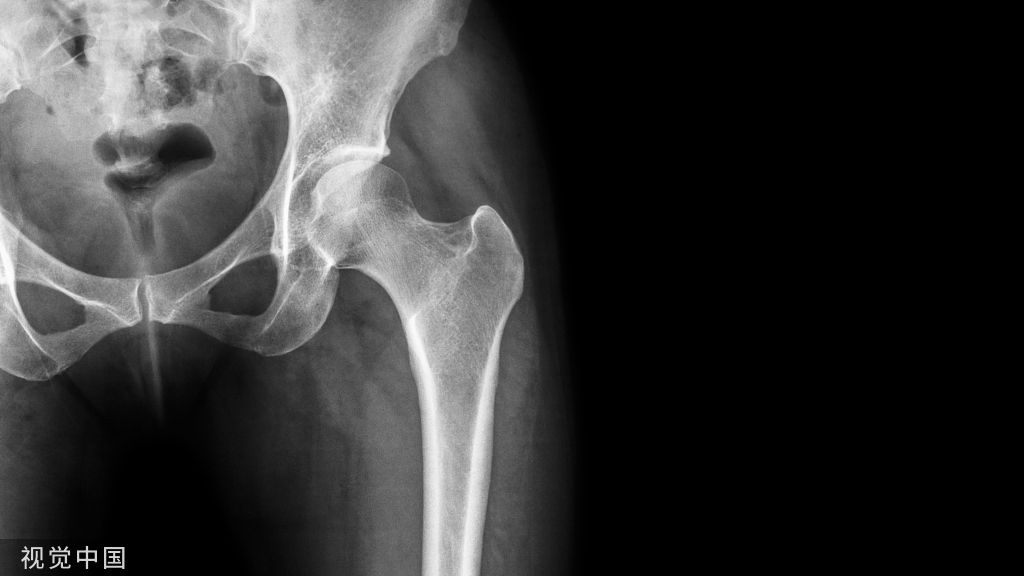

再来一张放大图像

X 线平片上表现为伴有清晰薄层硬化缘的环形(囊状)透亮区,CT 上表现为圆形 或类圆形的皮质下局灶性骨质缺损,周围见薄层硬化带环绕 边缘锐利,部分较大病灶在病灶层面或上下相邻 、层面上前方显示皮质与病灶相通的局部裂隙样缺损病灶,最大径线通常小于 10 mm;MRI 示病灶在 T1WI 上呈低信号,在 T2WI 上呈均匀或不均匀高信号。